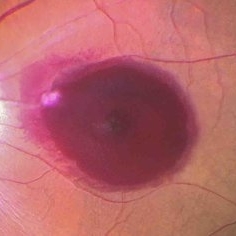

RPE rip in a case of Idiopathic polypoidal choroidopathy RPE rip in a case of Idiopathic polypoidal choroidopathyOct 23 2022 by Anjana Mirajkar, MS Ophthalmology Color photo central image in a of 61 year old male with RPE rip in a case of Idiopathic Polypoidal Choroidopathy. Photographer: Dr. Anjana Mirajkar -Retina Foundation, Ahmedabad Condition/keywords: idiopathic polypoidal choroidopathy, RPE Rip